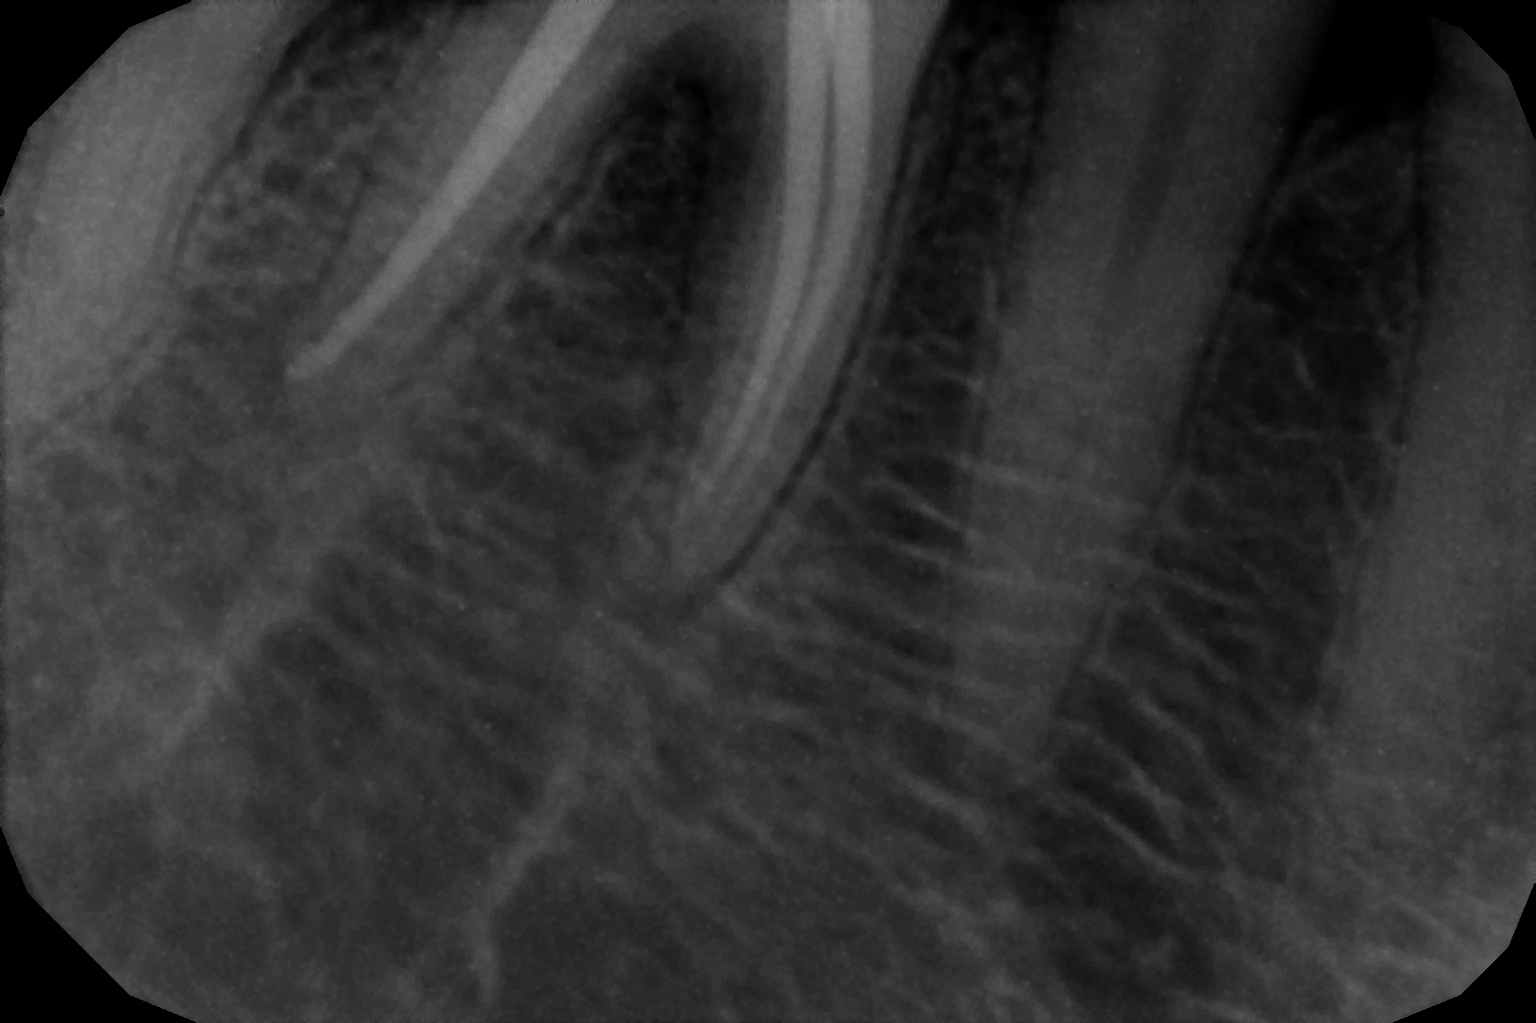

When the tooth is is sensitive to particularly hot and cold. When you cannot chew from that side or there is associated action of pain and swelling with same tooth, root canal treatment can save the tooth. For root canal treatment our clinic is equipped with state-of-the-art facility. We are following the protocol that is universally accepted and considered as a gold standard We are using rubber Dam for maximum possible cases. The root canal treatment is done under local anaesthesia that's why mostly it is painless . The rubber Dam isolation helps in proper irrigation and it provides much needed ease to the operating dental surgeon and the patient . The sealer and filling material are one of the Prime requisite of quality root canal treatment, it needs use of multiple X rays to really judge whether the results are acceptable or not. In older days root canal was just about cleaning the decade portion, removing the Pulp and filling it with biocompatible material but nowadays the root canal treatment it is very much advanced the precision is increased manifold. The materials and armamentarium that is required for efficient root canal have advanced in exclusion initial ways the the Abstract of all these things is the patients are getting great results after root canal treatment. Only the root canal is not sufficient to make a tooth functional again ,it needs use of Core buildup material and complete coverage Crowns according to the tooth position. During Covid19 time we have studied and implemented use of of high strength composites in our practice and the results of it are amazing many times it has saved tooth from being restored with crown. In some cases where the tooth is grossly carious we need a complete coverage crown. The materials and the Crown materials are are available in various price ranges. We prefer only the best of materials for our patients. We believe that to perform best treatment we need best of the armamentarium and best of the material for our patients who value and deserve the best of the treatment.